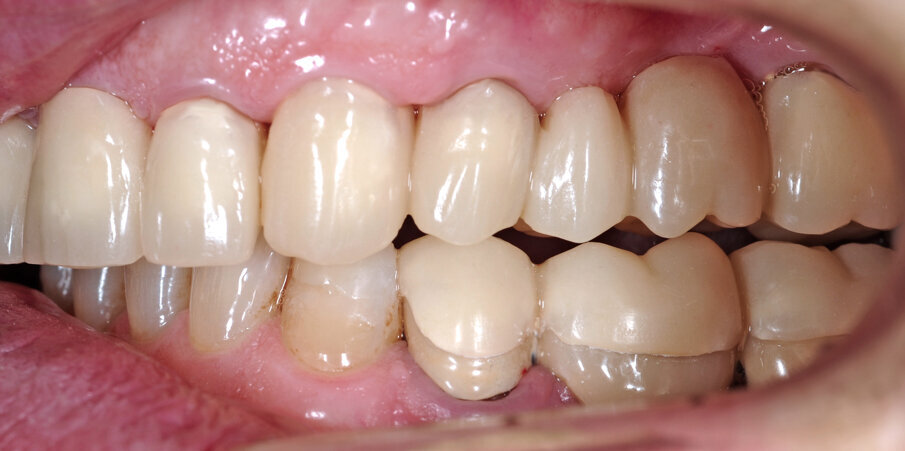

Un paziente di 66 anni, con anamnesi patologica di NIDDM ben compensato e cardio-vasculopatia ischemica in buon compenso farmacologico, si presenta alla nostra attenzione per ascesso parodontale alla radice residua del dente 1.2 e per multiple fratture dei manufatti protesici esistenti (Figg. 1-6). È evidente la presenza di grave malocclusione con perdita di VDO, usure e fratture dei restauri protesici e dei denti residui, presenza di abfractions cervicali. Il paziente evidenzia alla visita modesta dolenzia muscolare alla palpazione, specie a carico dei muscoli pterigoidei mediali e temporali, apertura della bocca ridotta e lieve rumorosità delle TMJ.

L’infezione a carico della radice del dente 1.2 è immediatamente attribuibile a frattura verticale con sondaggio positivo di 9 mm (Fig. 7). Estratta la radice di 1.2 fratturata, il paziente richiede una riabilitazione protesica fissa all’arcata superiore che preveda il minor numero possibile di interventi endodontici e chirurgici. Viene da noi proposta una riabilitazione protesica full arch che consenta, previo studio del caso gnatologico e terapia interlocutoria con provvisori in PMMA, la definizione di un’occlusione a funzione sequenziale in TRP per l’aumento controllato della VDO e la stabilizzazione dei rapporti articolari, ora visibilmente compromessi.